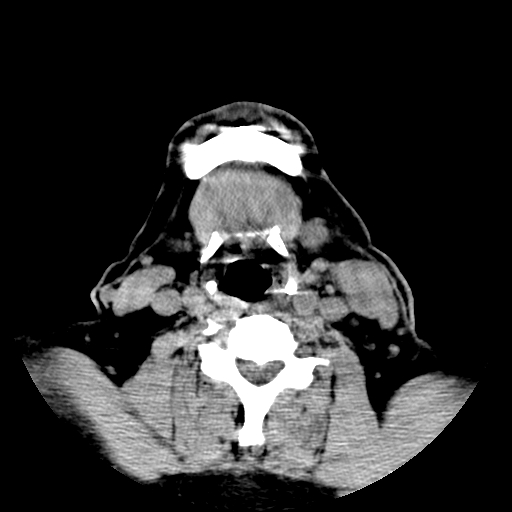

以下是引用卜一在2007-8-6 21:23:00的发言:[br]定位:左侧胸锁乳突肌内侧 颌下腺下后方。特征:弥漫性生长 软组织密度肿块,界限不清,内隐约见低密度坏死。考虑:神经源性肿瘤或血管源性肿瘤。

以下是引用wangzhanshuang在2007-8-6 21:08:00的发言:[br]腮腺混合瘤